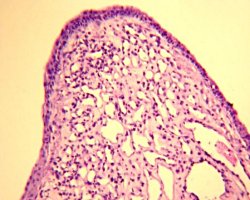

Патоморфологическим субстратом новообразования являлась гемангиома, покрытая респираторным эпителием.